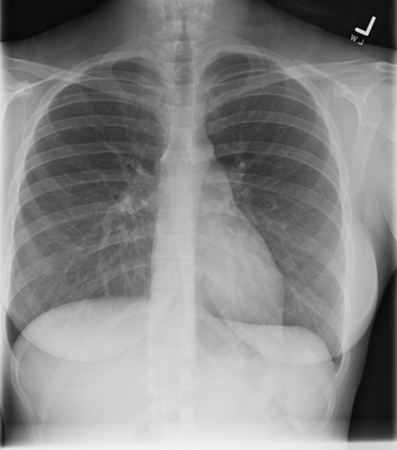

Penetration

Under-penetration results from not enough xrays passing thru to allow differentiation of dense structures, thus the mediastinum and spine appear white. In an over-penetrated CXR too many xrays have passed thru the chest preventing differentiation of low density structures, thus the lung fields appear black. With proper penetration, the spine should be faintly visible behind the heart.

Under-penetrated Over-penetrated Correctly-penetrated